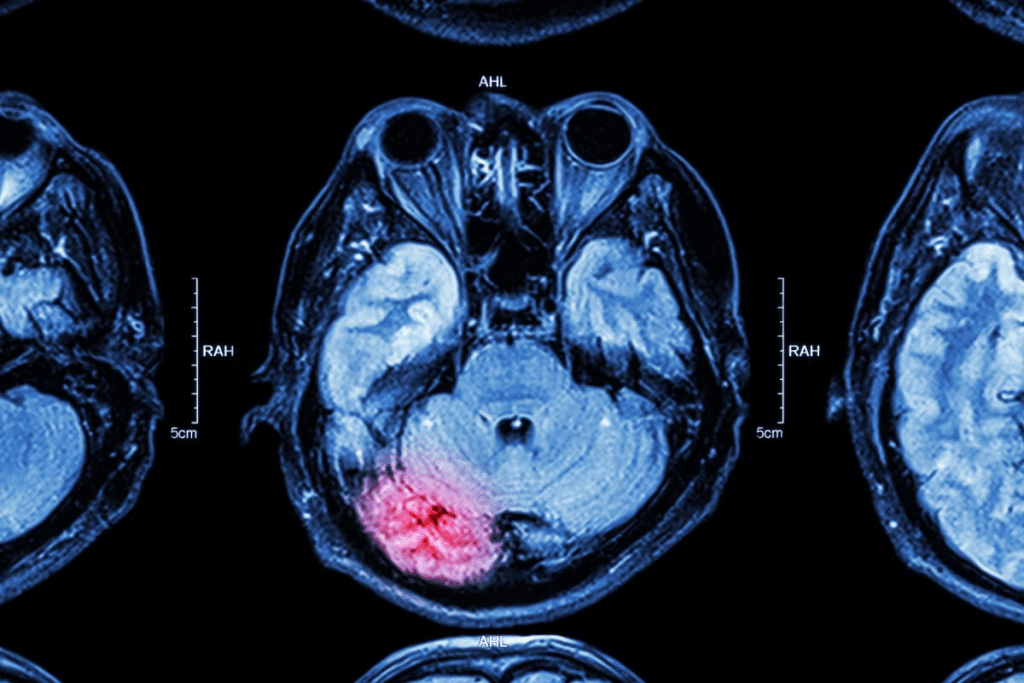

An MRI (Magnetic Resonance Imaging) scan shows detailed images of the body’s inside parts. This includes joints, blood vessels, and organs. Doctors use MRI scans to find out what’s wrong and decide the best treatment.

The process starts with the MRI machine capturing detailed brain images. These images are then sent to a radiologist for review. The radiology technician ensures the images are of high quality and are sent correctly.

The radiologist checks the MRI and brain images for any issues. This step is vital for diagnosis and treatment planning.

An MRI scan is a non-invasive way to see inside the body. It helps doctors find and track injuries, cancers, and brain disorders. It shows detailed pictures of the body’s internal parts.